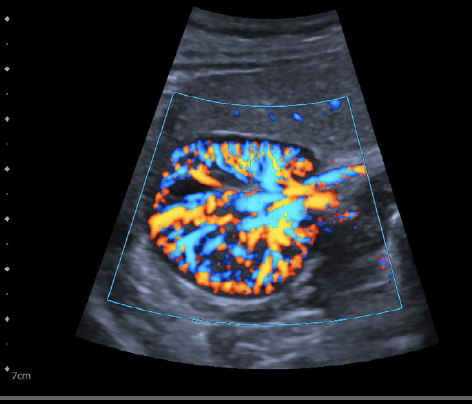

07. ​Digital Ultrasound

Harnessing next-generation BioAcoustic technology, the Sequoia system penetrates deeper with exceptional sensitivity—revealing subtle variations in tissue elasticity, vascular flow, and organ density. Its precision in liver, cardiac, and breast elastography allows Digital Intelligence to detect early micro-imbalances invisible to the human eye.

AI-Driven Cardiac Ultrasound built for cardiovascular excellence integrates more than 5,600 AI-powered measurements informed by nearly two billion cardiac images. Real-time HeartAI mapping provides fully automated view recognition and quantification, reducing human error and standardizing insight across users and systems.